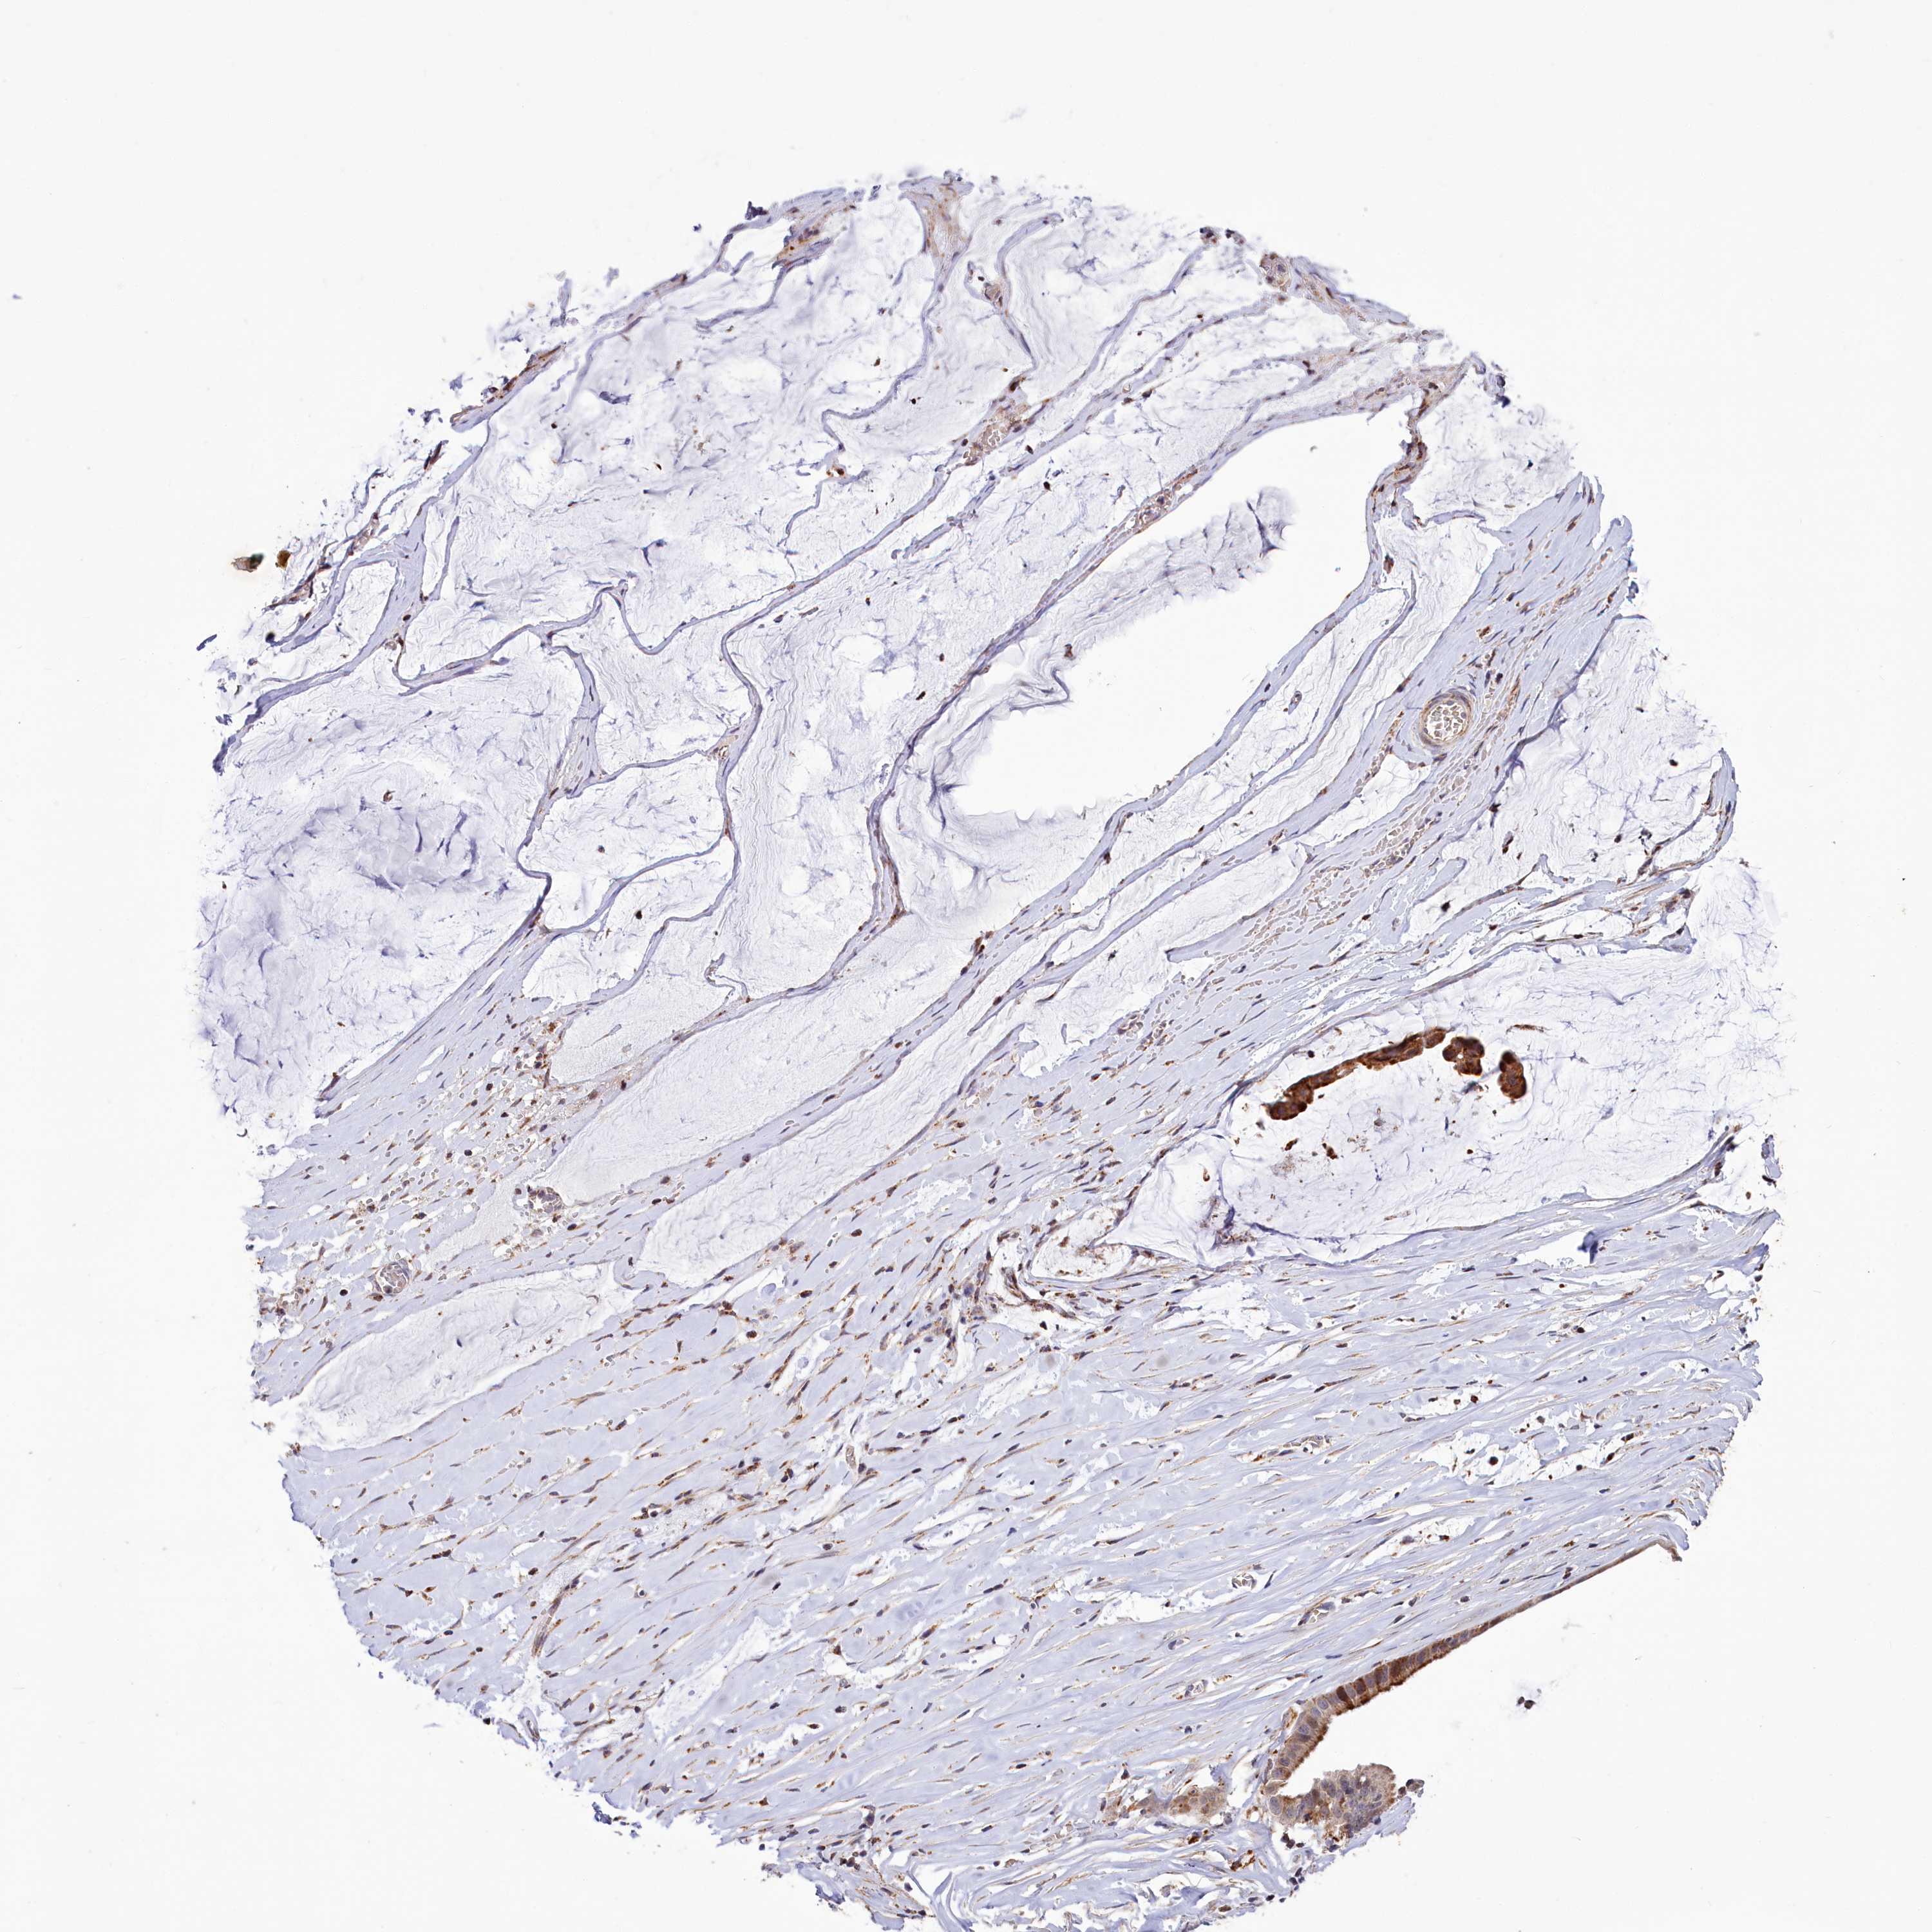

OVARIAN CANCER - Protein expressioni

A mouse-over function shows sample information and annotation data. Click on an image to view it in a full screen mode. Samples can be filtered based on level of antibody staining by selecting one or several of the following categories: high, medium, low and not detected. The assay and annotation is described here.

Note that samples used for immunohistochemistry by the Human Protein Atlas do not correspond to samples in the TCGA dataset.

Antibody stainingi

Antibody staining in the annotated cell types in the current human tissue is reported as not detected, low, medium, or high, based on conventional immunohistochemistry profiling in selected tissues. This score is based on the combination of the staining intensity and fraction of stained cells.

Each image is clickable and will lead to virtual microscopy that enables deeper exploration of all samples and also displays staining intensity scores, fraction scores and subcellular localization as well as patient and tissue information for each sample.

Antibody HPA039015

Antibody HPA039016

Cystadenocarcinoma, serous, NOS

Carcinoma, endometroid

Cystadenocarcinoma, mucinous, NOS

Carcinoma, NOS